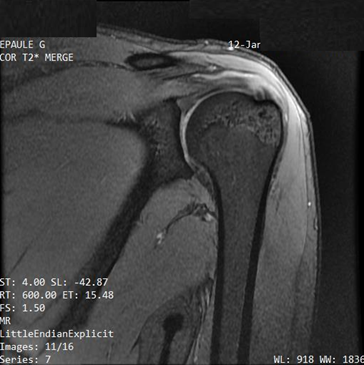

Biology showed a mild inflammatory syndrome with an erythrocyte sedimentation rate of 39mmH1 and a C-reactive protein of 10mg/l. Complete blood count, uric acid, serum calcium, creatinine, muscle enzymes, blood glucose, lipid parameters, transaminases, plasma protein electrophoresis, urine sediment analysis, and thyroid hormones were within limits from normal. The radiograph of the left shoulder showed widening of the juxta-articular soft tissues without bone lesions. Ultrasound of the shoulder showed intra-articular effusion in the bicipital gutter and subacromial-deltoid bursa of moderate abundance, hypoechoic and heterogeneous and without tendon lesions. MRI confirmed subacromial-deltoid bursitis (minimal effusion in the bursa with spontaneous T2 hypersignal and T1 hyposignal) (Figures 1 & 2) with signs of minimal tendinopathy at the supraspinatus insertion.

Figure 1 MRI of the left shoulder, lateral T2-weighted view: spontaneous hypersignal of the subacromial-deltoid bursa (bursitis).